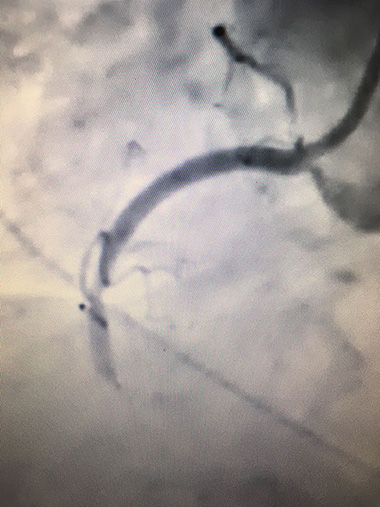

Invasive coronary angiogram showing a blocked right coronary artery